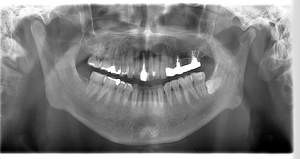

インプラント治療の症例1

レントゲン写真

- 透過像

| 年齢 | 50代・男性 |

|---|---|

| 主訴 | 右下歯が疼く |

| 治療内容 | ・右下6番インプラント ※1:FGG(遊離歯肉移植術)とは、足りない歯ぐきを上顎から上皮を切り取り移植する外科手術 |

| 治療費 | 合計:902,000円(税込) ■内訳 |

| 治療期間 | 9ヵ月 |

| 治療方針 | 右下の当該歯は歯根破折により保存不可能と診断しました。歯周疾患も伴っていたため抜歯後に骨吸収※1が大きく起こることが予測できました。チタンメッシュ併用骨再生誘導法(GBR※2)を選択しインプラント埋入と同時に行い自然な歯槽骨のラインを再現しました。またGBRを行う際にインプラント辺縁の付着歯肉の減少が起こる為、遊離歯肉移植術(FGG※3)を行い清掃性を考慮した形態に仕上げました。 ■治療方針の解説 治療した右下の歯をレントゲンで撮影したところ根本の部分に黒く写る箇所があり「根尖性慢性周囲炎※1」と診断。また歯周病も進行していました。 ※1 骨吸収・・・歯槽骨という歯を支える骨がなくなっていくこと |

| 担当者所見 | 主訴の右下だけでなく歯茎の腫れ、発赤があり不良補綴や不良充填など他にも治療箇所が多数ありました。プラークコントロールが不良であった為まずはブラッシング指導を行いセルフケアの重要性を理解していただくところからスタートしました。 右下6番の歯はインプラント治療を行なった結果審美的にも機能的にも患者様の満足を得ることができました。骨造成と歯肉移植も行なった為インプラントを支える十分な歯周組織の獲得ができたと思っております。 |